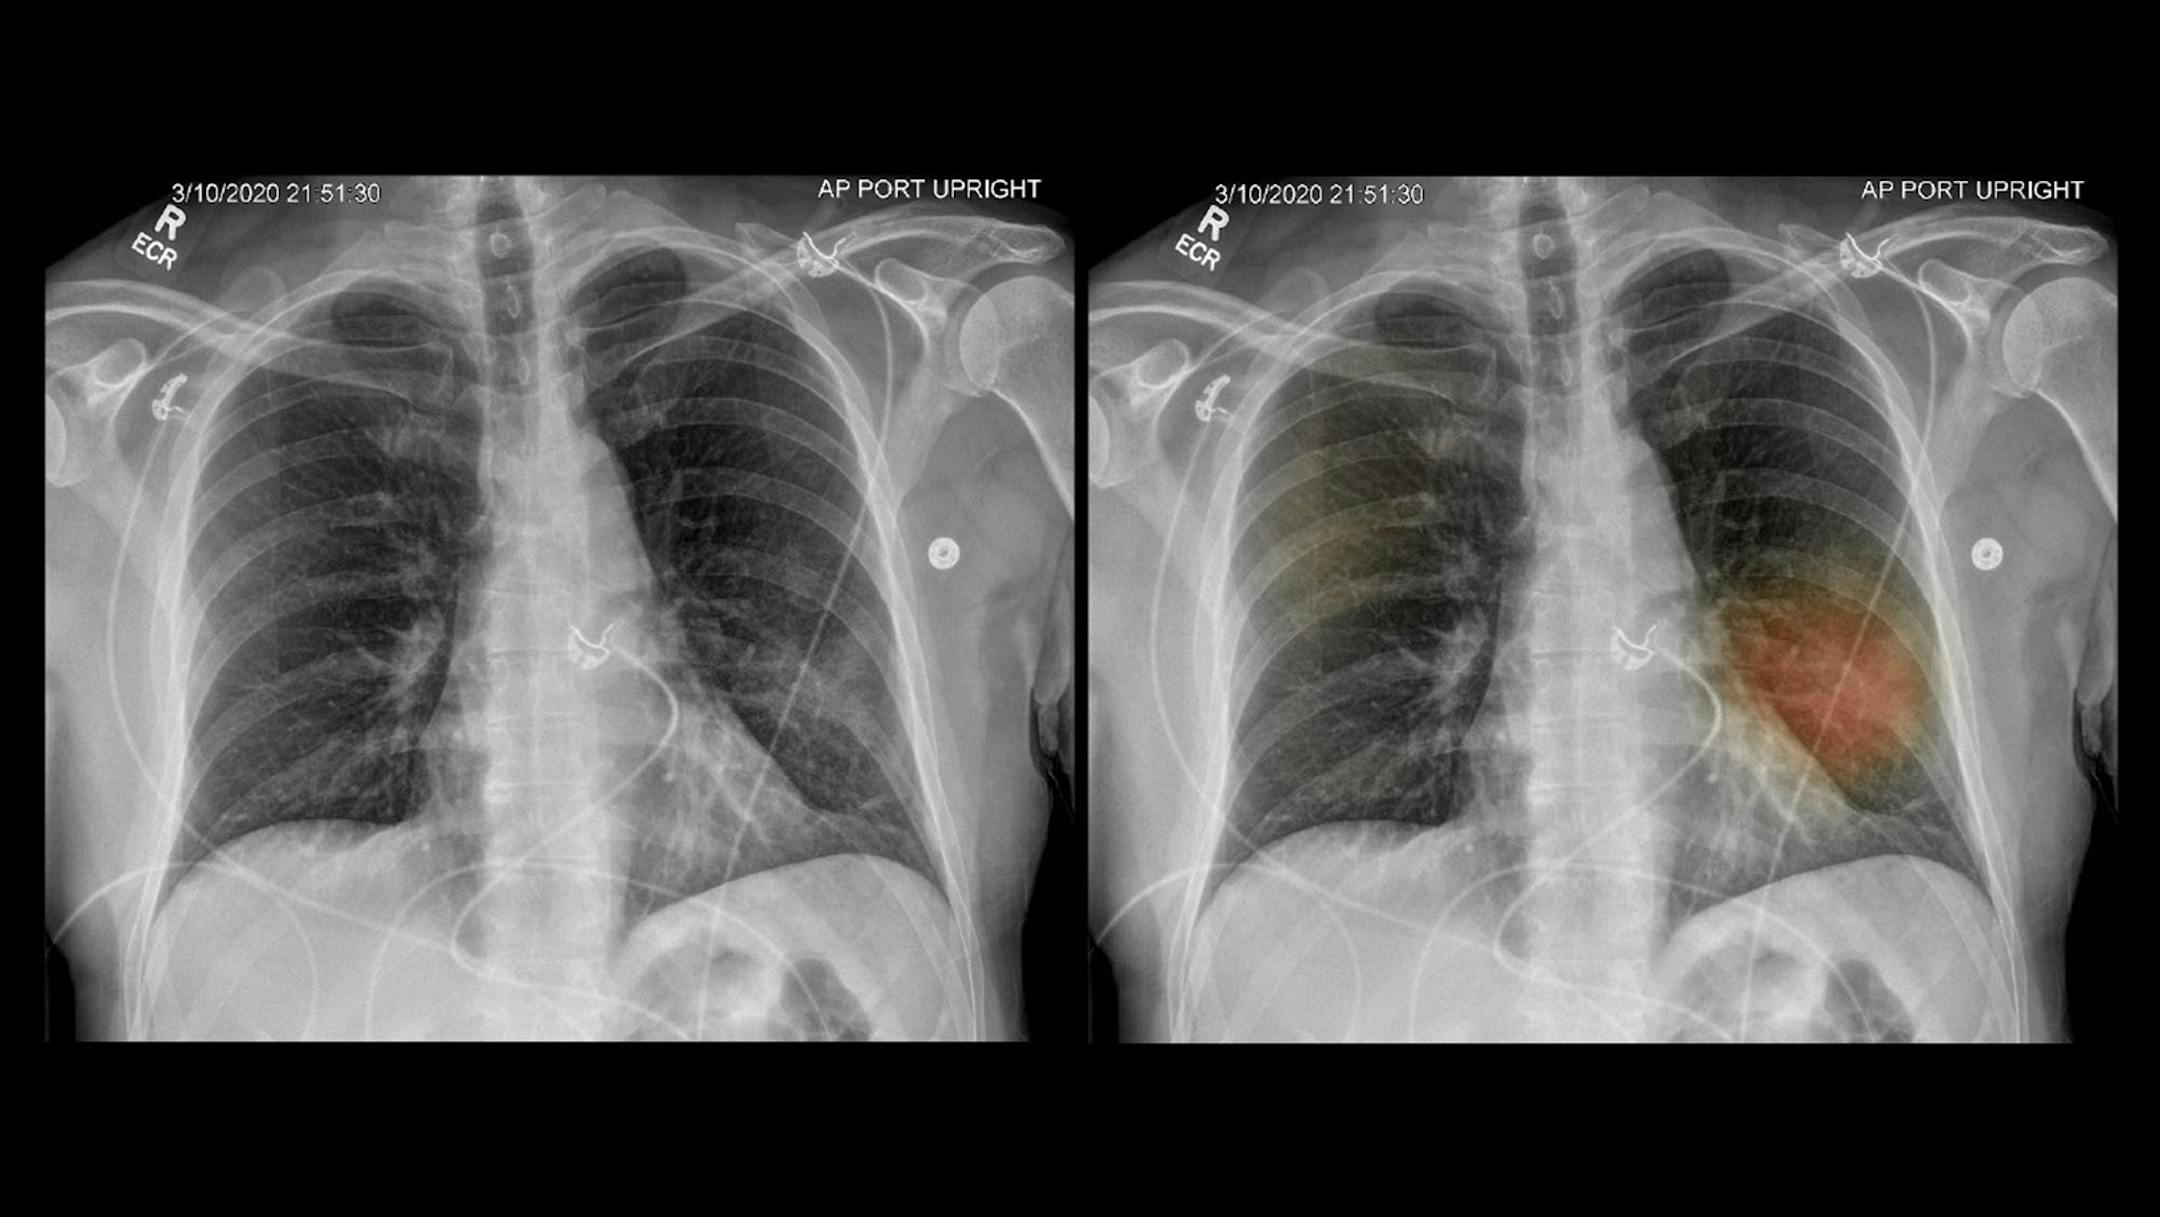

Two X-ray images show a patient's diseased lungs. Using an artificial intelligence program developed by UC San Diego Health system, the image on the right has been dotted with spots of color indicating where there may be lung damage or other signs of pneumonia. (Courtesy of Dr. Albert Hsiao/KHN/TNS)

Using an artificial-intelligence program, the image on the right has been dotted with spots of color indicating where there may be lung damage or other signs of pneumonia. (The Minnesota Star Tribune)